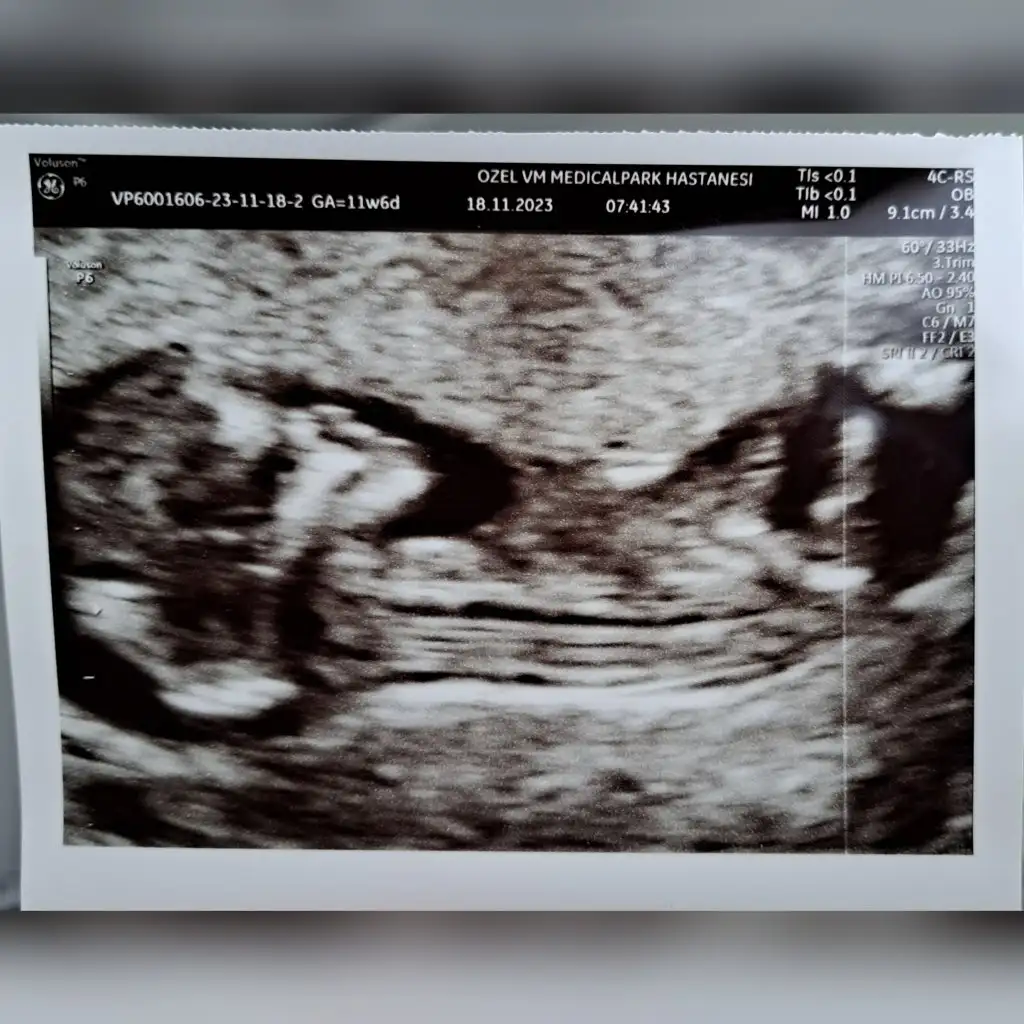

dr soylemeden siz gorun genital nub teorisi ( bebegin cinsiyeti)

13+6 nubu kız gibi ama bacak arasında da çıkıntı var gibi sizin tahmininiz nedir

Eklentiler

• Screenshot_2023-11-21-20-22-33-531_com.miui.gallery.webp

17,7 KB · Görüntüleme: 126

• Screenshot_2023-11-21-20-21-29-746_com.miui.gallery.webp

19 KB · Görüntüleme: 116

• Screenshot_2023-11-21-20-20-53-023_com.miui.gallery.webp

18,8 KB · Görüntüleme: 105